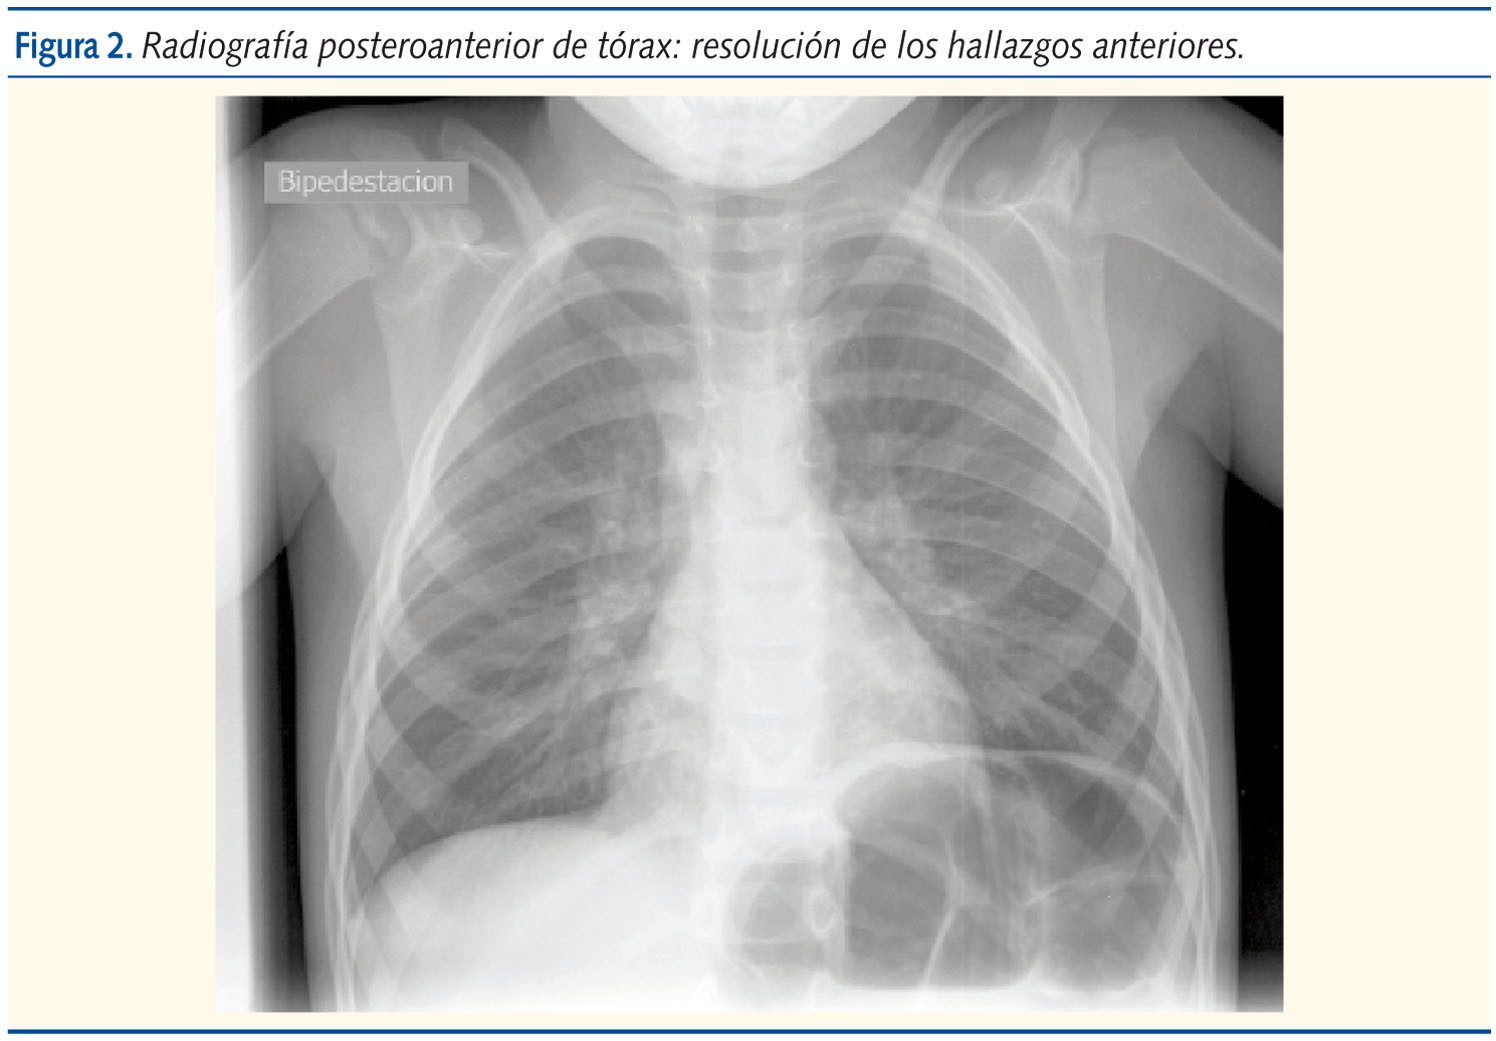

Con el diagnostico de síndrome de Chilaiditi, se inicia tratamiento conservador con dieta y laxantes, siendo valorado a las 24 y 48 horas; el paciente elimina gases y heces a las 24 horas. Desde entonces permanece asintomático.

Se realiza una radiografía de control a los siete días, en la que ha desaparecido la interposición colónica entre el diafragma y el hígado (figura 2).